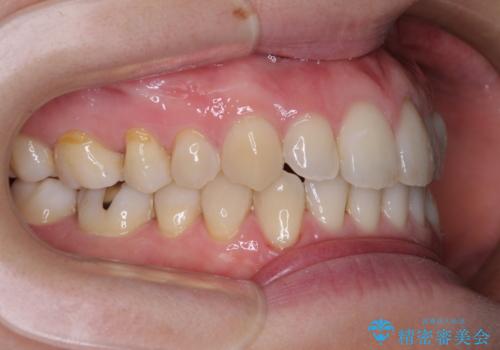

- 受け口傾向でクロスバイトの前歯を治したいとのことで来院された患者様です。

下顎骨が若干左側に変位していたため、右側にアンカースクリューを使用し、積極的に移動させながらインビザラインにて矯正治療を行うこととしました。

インビザラインによる矯正治療は、受け口傾向の治療に非常に適した方法であり、事前にシミュレーションに沿って治療を進めることできます。

今回の治療では骨格的な偏位があったためアンカースクリューを使用し、より確率の高い治療を行うことができました。